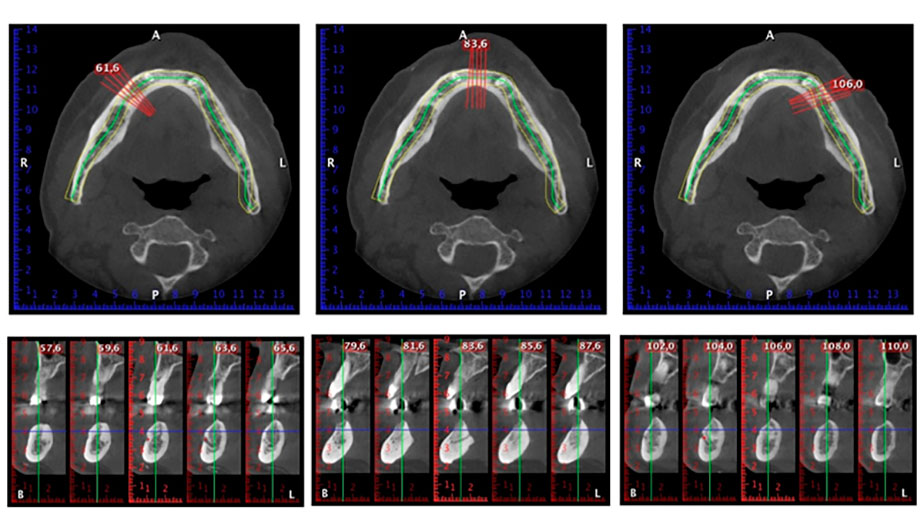

Zur Planung und Risikominimierung wurde eine dreidimensionale Volumentomografie (DVT, Planmeca) erstellt. Dieses zeigte, dass die Qualität und Quantität des Knochens für eine Operation und Sofortversorgung nach der Fast & Fixed-Methode ausreichend war. Nach Protokoll dieses Konzeptes wird in Regio 35, 32, 42 und 45 implantiert. Durch die bis zu 45-Grad-Schiefstellung der distalen Implantate wird das Durchtrittsprofil nach posterior verlegt und ein größeres Stützpolygon erreicht (Abb. 3).

Fast & Fixed-Methode

Abb. 3